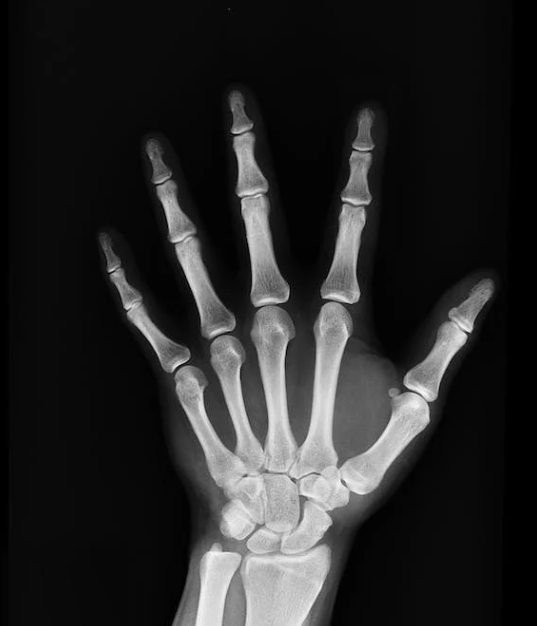

1. 양성 골종양 :성장 속도가 느리고, 자각 증상이 나타나지 않는다. 종양은 경계가 분명하고 압통이 없다. 종양이 성장하여 해당 부위의 기능 손실을 초래할 정도가 되어서야 발견되는 경우가 많다.

2. 악성 골종양 :성장 속도가 빠르고 통증이 있다. 통증의 정도가 처음에는 약하고 간헐적이다 나중에는 심해지고 지속적으로 나타난다. 종양의 경계는 불분명하고 압통이 있다. 악성 골종양 중 골육종의 경우 팔다리의 통증과 종창(부종)이 나타난다.